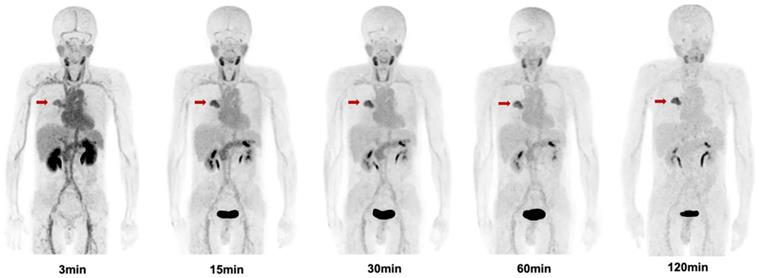

Figure 6

Maximum intensity projection (MIP) images of [68Ga]Ga-FAPI-RGD at 3,15, 30, 60, and 120 min post injection in a patient with lung cancer (Lung cancer lesions are indicated by red arrows).

The biodistribution of [68Ga]Ga-FAPI-RGD in normal organs and tumor is presented in Figure 6 and illustrated as time-dependent maximum-intensity projections in Figure 7. The physiological biodistribution of [68Ga]Ga-FAPI-RGD involved the thyroid glands, salivary glands, pancreas, kidneys, liver, heart content, spleen, and urinary bladder. The SUVmax of normal organs decreased in all patients over time, except for the bladder. [68Ga]Ga-FAPI-RGD PET/CT demonstrated intense radioactivity in the urinary tract, indicating that the kidneys were the main excretory organs. The highest average normal organ SUVmean at all time points was observed in the thyroid glands, decreasing from an average SUVmean of 7.8 at 3 min to 3.0 by 2.0 h (decline of 62.5%).

Tracer uptake in the tumor was rapid and showed a steady increase in SUV values with an average SUVmax of 7.0 at 3 min, 8.0 at 15 min, 8.0 at 30 min, 8.3 at 60 min and 9.1 at 2 h, respectively. Meanwhile, the TBRs increased significantly to a much higher level with time (with exception of the gallbladder TBR) due to the SUVmax of the organs decreased over time. The TBR (blood) was 2.7 at 15 min, 4.1 at 60 min, and 6.9 at 2 h. The TBR (liver) was 5.0 at 15 min, 6.7 at 60 min, and 9.7 at 2 h, higher than TBR (blood). The lesions could be clearly visualized at the early 15-min scan, which became clearer at the 1-h and 2-h scans.